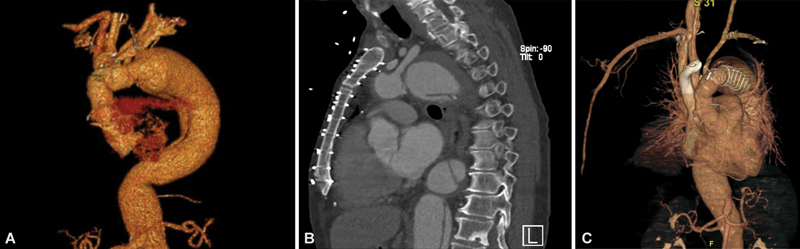

Abstract Image